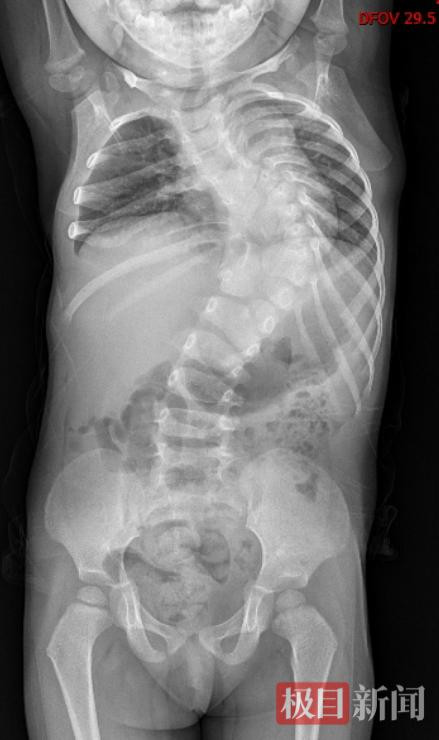

可可(化名)今年12岁,家住新洲。从一出生起,她就患有先天性椎体发育畸形,脊柱向左倾斜,身体扭曲。2岁时,可可脊柱倾斜度数达到了90度,上半身几乎被“折”成了直角。父母带可可四处求医,可都因为畸形严重且复杂,矫形难度大,年龄小且治疗周期长,未来治疗存在不可预测性,迟迟没能得到有效救治。

2015年第一次就诊时,当时的脊柱折成了90度